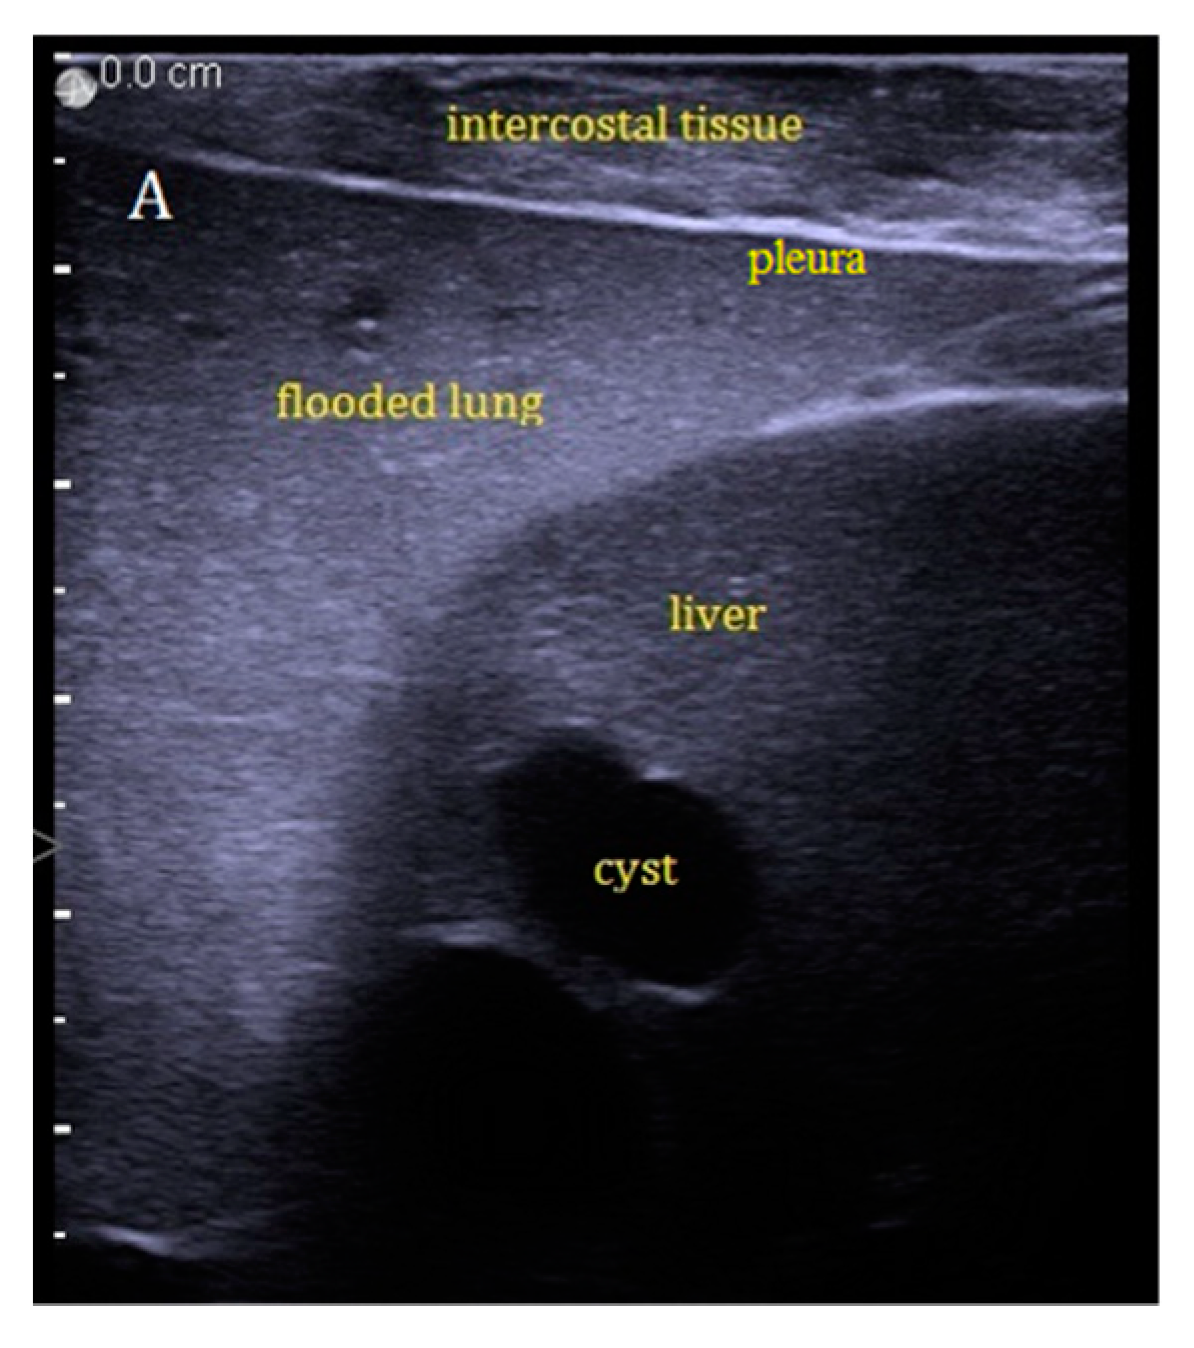

During stable flooding in-vivo with saline, unimpaired imaging without remaining air was achieved. The lung parenchyma appears homogeneous with enhanced echogenicity, where vessels and bronchi are well demarked as hypoechoic structures [18]. Trans-pulmonary imaging visualized adjacent organs such as the liver or heart (Figure 4). Doppler imaging in flooded lung is feasible and useful to detect vessels (Figure 5). No limitations regarding penetration depth were documented. High frequency linear probes (10–15 MHz) were recommended for high resolution imaging such as for small bronchi or vessels [22] (Figure 6). Using ex-vivo models and simulated intra-pulmonary nodules in-vivo, a reliable nodule detection of primary lung cancer as well as metastases were found. The tumor mass appears hypoechoic, surrounded by hyperechoic flooded lung, resulting in a high detection rate of about 100% of malignant pulmonary nodules (Figure 7), as well as simulated nodules [31]. Interestingly, the visualization is aggravated only for the bronchoalveolar cell carcinoma. The specific growth along the alveolar surface caused an echo-enhanced appearance with similar characteristics to flooded lung parenchyma [18].

Figure 4. Sonographic imaging during OLF in-vivo with clear visualization of hyperechoic lung, well demarked from hypoechoic liver.